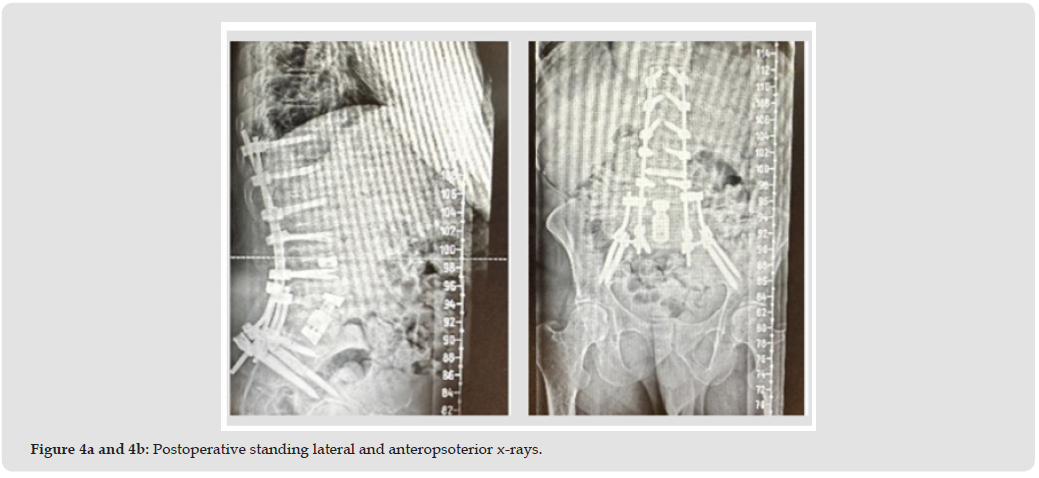

The patient is a 36-year-old male (BMI 18) with a history of ongoing intravenous drug abuse presenting with severe spinal deformity, inability to stand upright, and protracted pain. The patient’s disability has progressed to the point of inability to perform activities of daily living. On physical examination, the patient demonstrates approximately 60 degrees of lumbar which is rigid on range of motion testing. Weakness of the bilateral quadriceps, anterior tibialis and gastrocnemius is present on manual muscle testing. Lumbar CT imaging is significant for severe destruction of the L3, L4 and L5 vertebral bodies (Figures 1a & 1b). The patient was indicated for 3-level lumbar corpectomy from a posterior approach with fixation from T10 to pelvis. Intraoperative cultures were positive for methicillin-resistant Staphylococcus aureus. A titanium corpectomy cage filled with (Sur- GenTec Osteoflo® Hydrofiber) (Figure 2) was placed from L2 to S1 for anterior column stabilization (Figure 3a). Osteoflo® Hydrofiber was reconstituted with saline only and used stand-alone. Postoperative x-ray (Figures 4a & 4B) imaging confirmed appropriate deformity correction and CT imaging at 8 months confirmed fusion (Figure 3b) from L2-S1 through the corpectomy cage.

Procedure: Posterior approach L2–S1 reconstruction, including three-level lumbar corpectomy and fixation from T10 to pelvis. Intraoperative cultures were positive for MRSA. A titanium corpectomy cage was filled entirely with Osteoflo® Hydrofiber, reconstituted with saline.